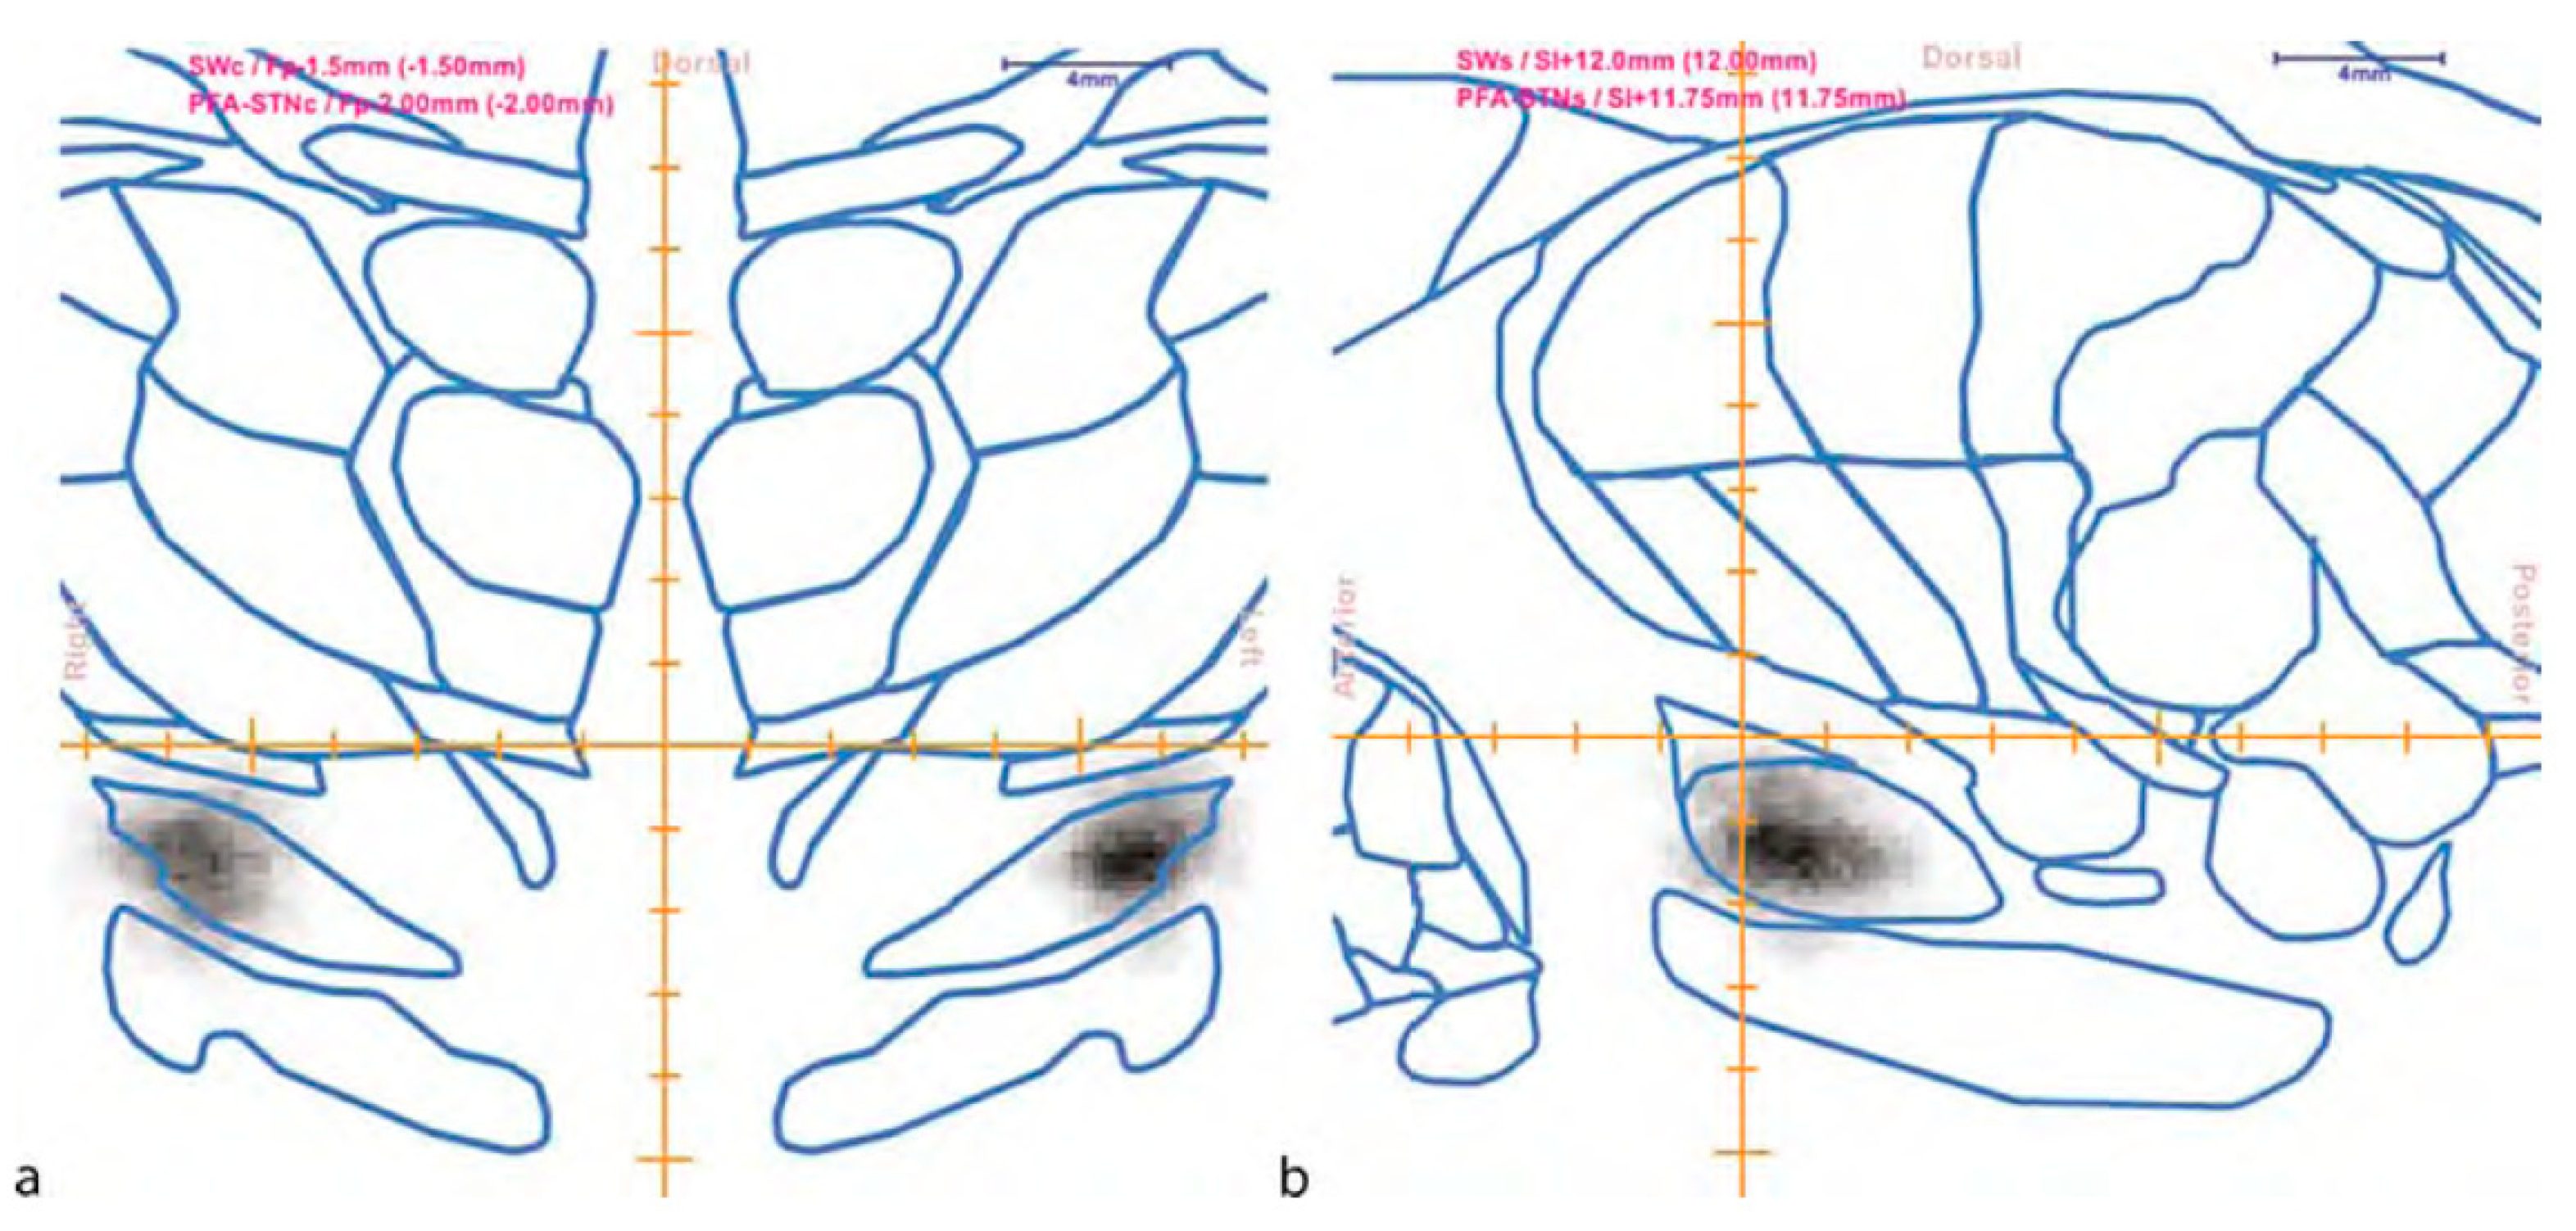

8. Digital Histological Atlases

- Nowinski, W.L.; Belov, D.; Benabid, A.L. An Algorithm for Rapid Calculation of a Probabilistic Functional Atlas of Subcortical Structures from Electrophysiological Data Collected during Functional Neurosurgery Procedures. Neuroimage 2003, 18, 143–155. [Google Scholar] [CrossRef]

- Nowinski, W.L.; Belov, D.; Pollak, P.; Benabid, A.L. A Probabilistic Functional Atlas of the Human Subthalamic Nucleus. Neuroinformatics 2004, 2, 381–398. [Google Scholar] [CrossRef]

- Nowinski, W.L.; Belov, D.; Thirunavuukarasuu, A.; Benabid, A.L. A Probabilistic Functional Atlas of the VIM Nucleus Constructed from Pre-, Intra- and Postoperative Electrophysiological and Neuroimaging Data Acquired during the Surgical Treatment of Parkinson’s Disease Patients. Ster. Funct. Neurosurg. 2005, 83, 190–196. [Google Scholar] [CrossRef]